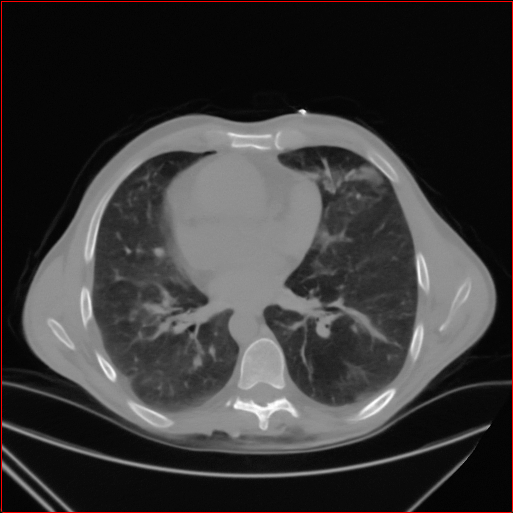

Figure 2: Qualitative comparison across axial (top row), sagittal (middle row), and coronal (bottom row) views. Columns correspond to different methods. MAISI-DDPM and MAISI-v2 in this figure are unconditional synthesis which do not use ControlNet or segmentation maps.

Qualitative Evaluation:

Figure 2 presents representative slices from the axial, sagittal, and coronal planes. GenerateCT (Hamamci et al. 2024) is a 2D model, so it lacks inter-slice consistency, leading to poor image quality in the sagittal and coronal views. MedSyn (Xu et al. 2024) produces noticeably blurry results with mosaic-like artifacts, such as region inside the red box. HA-GAN (Sun et al. 2022) generates visually sharp images but with mosaic-like artifacts, such as region inside the red box. Also, its voxel spacing is not available, which limits its applicability in real-world medical imaging tasks. Moreover, all three methods are restricted to synthesizing small anatomical regions. In contrast, both MAISI and MAISI-v2 are capable of generating high-quality 3D volumes that span larger body regions while preserving fine anatomical details and realistic structure.